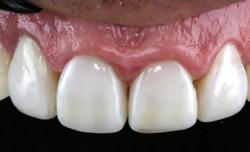

Before whitening.

Upper teeth after 5 nights of treatment with Opalescence PF 10% whitening gel, approximately 40 hours.

Before whitening; new restorations are planned.

After 8 days of treatment with Opalescence PF 16% whitening gel, every day for 3 hours.

After 6 days of treatment with Opalescence PF 10% whitening gel, every night for 8 hours. New composite restorations in place.

After one month of whitening.

Moderate to advanced tetracycline stains. Improvement in 2 weeks. With tetracycline stains, treatment can require 2 to 6 months.1